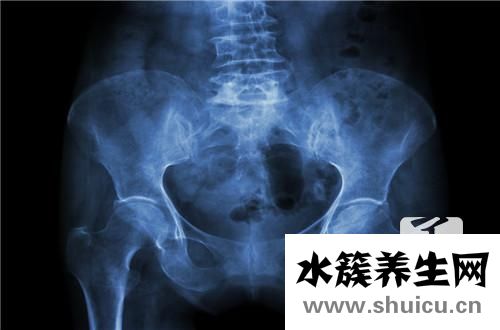

盆腔癌到了末期,癥狀會更明顯,如月經失調、小腹劇烈疼痛、胎兒腹圍增大增厚、腹痛等。當人體有明顯不適時,大家需要學會立即進行檢查。如果不能分辨自己,就需要去正規醫院做詳細的診斷,這樣就可以馬上...

盆腔 積液根據疾病級別盆腔 積液分為輕度和中度。那么骨盆體積小積液?這意味著盆腔 積液相對較小,愈合與盆腔血容量有一定的相關性。一般來說,如果盆腔 積液少一些,炎癥會輕一些;如果盆腔 積液更多,炎...